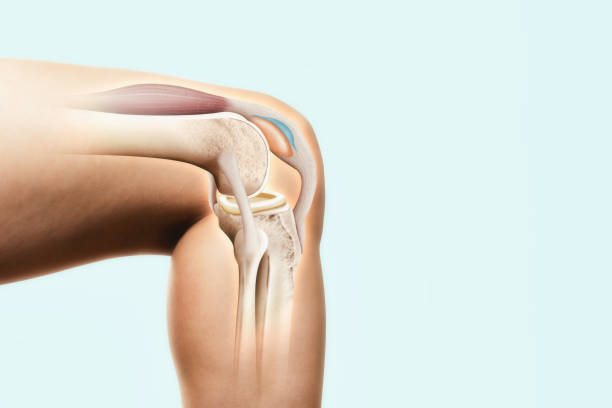

연골은 뼈와 뼈 사이의 마찰을 줄이고 충격을 흡수하는 기능을 합니다. 무릎의 연골손상은 무릎 통증의 일반적인 원인 중 하나입니다. 연골손상은 다양한 원인으로 발생할 수 있으며, 가장 흔한 원인은 무릎 관절 내의 충격이나 비대칭적인 압력에 의해 발생하는 외상입니다. 연골손상은 통증, 부종, 불안정성, 감각 손실 등의 증상을 일으킬 수 있습니다. 치료는 무릎 관절을 안정시키는 운동, 연골 재생을 촉진하는 약물 치료, 수술 등이 있습니다.

전방십자인대는 무릎을 지탱하는 중요한 인대 중 하나입니다. 이 인대가 파열되면 무릎이 불안정해지며, 걷거나 달리는 등의 운동 시 무릎이 흔들리거나 무력감이 느껴집니다. 무릎 통증, 부종, 불안정감 등의 증상이 나타나며, 복합적인 치료가 필요합니다. 치료에는 수술적 치료, 전문가의 지도하에 진행되는 재활 운동 등이 포함됩니다.

슬개골염은 슬개골 연골과 연결된 퇴행성 질환으로, 무릎 관절 내부에서 연골의 변성이 진행됨에 따라 발생합니다. 무릎 통증, 관절 강직, 충수성 부종 등의 증상을 일으키며, 보행이나 운동 시 통증이 더욱 심해질 수 있습니다. 치료는 운동 치료, 약물 치료, 수술적 치료 등이 있으며, 초기 단계에서 조기에 진단하고 치료를 시작하는 것이 중요합니다.